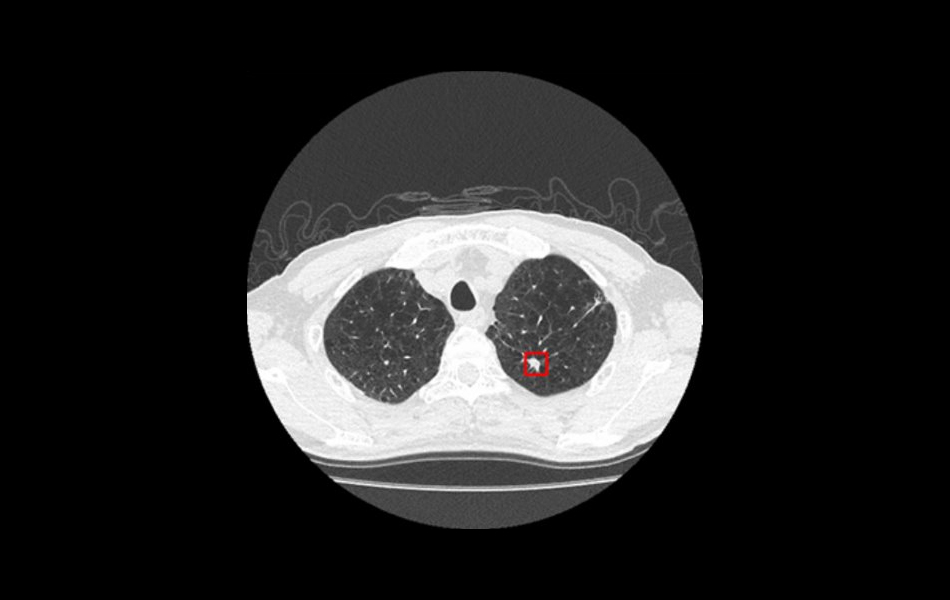

Lung CAD (7.15.8)

In addition to the Visia™ CT Lung CAD application by MeVis Medical Solutions that is offered as part of Vitrea Advanced Visualization, another option for Lung CAD is now available. The Lung CAD option highlights lung nodule locations per volume within CT Lung Analysis.